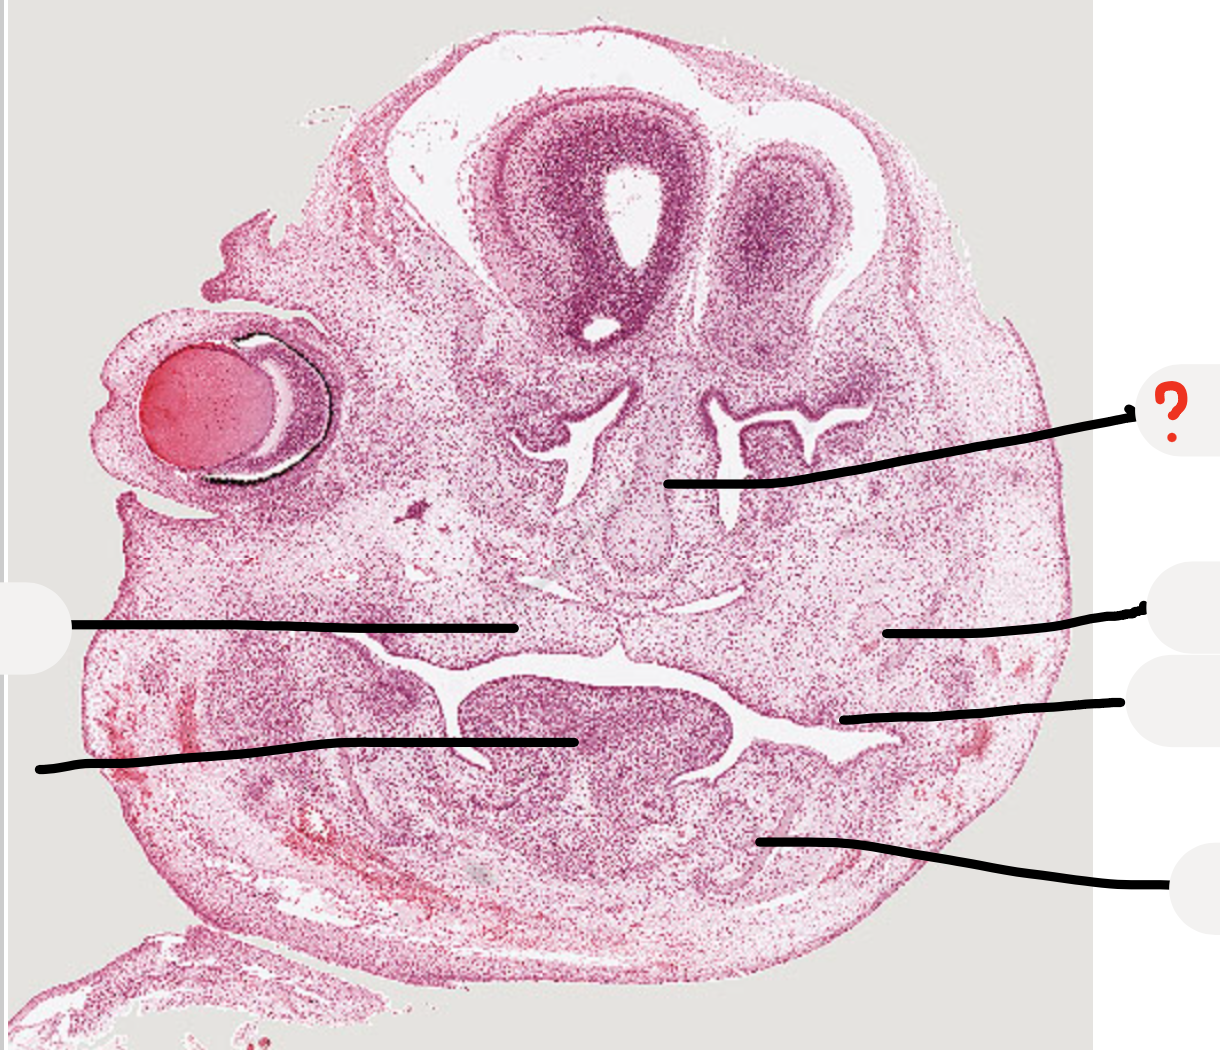

mandibular process

maxillary process

developing tooth -> dental lamina and tooth germ

meckel’s cartilage

tongue

palatal shelves

maxillary nerve trunk

early tooth development

nasal capsule

tooth germ

meckel's cartilage

developing mandible

inferior alveolar nerve

look at this inferior alveolar nerve next to the developing mandible

what are these?

Remnants of nasal capsule

Condensed ectomesenchymal cells that will make dentine and pulp

Epithelial cells that will form ameloblasts and make enamel